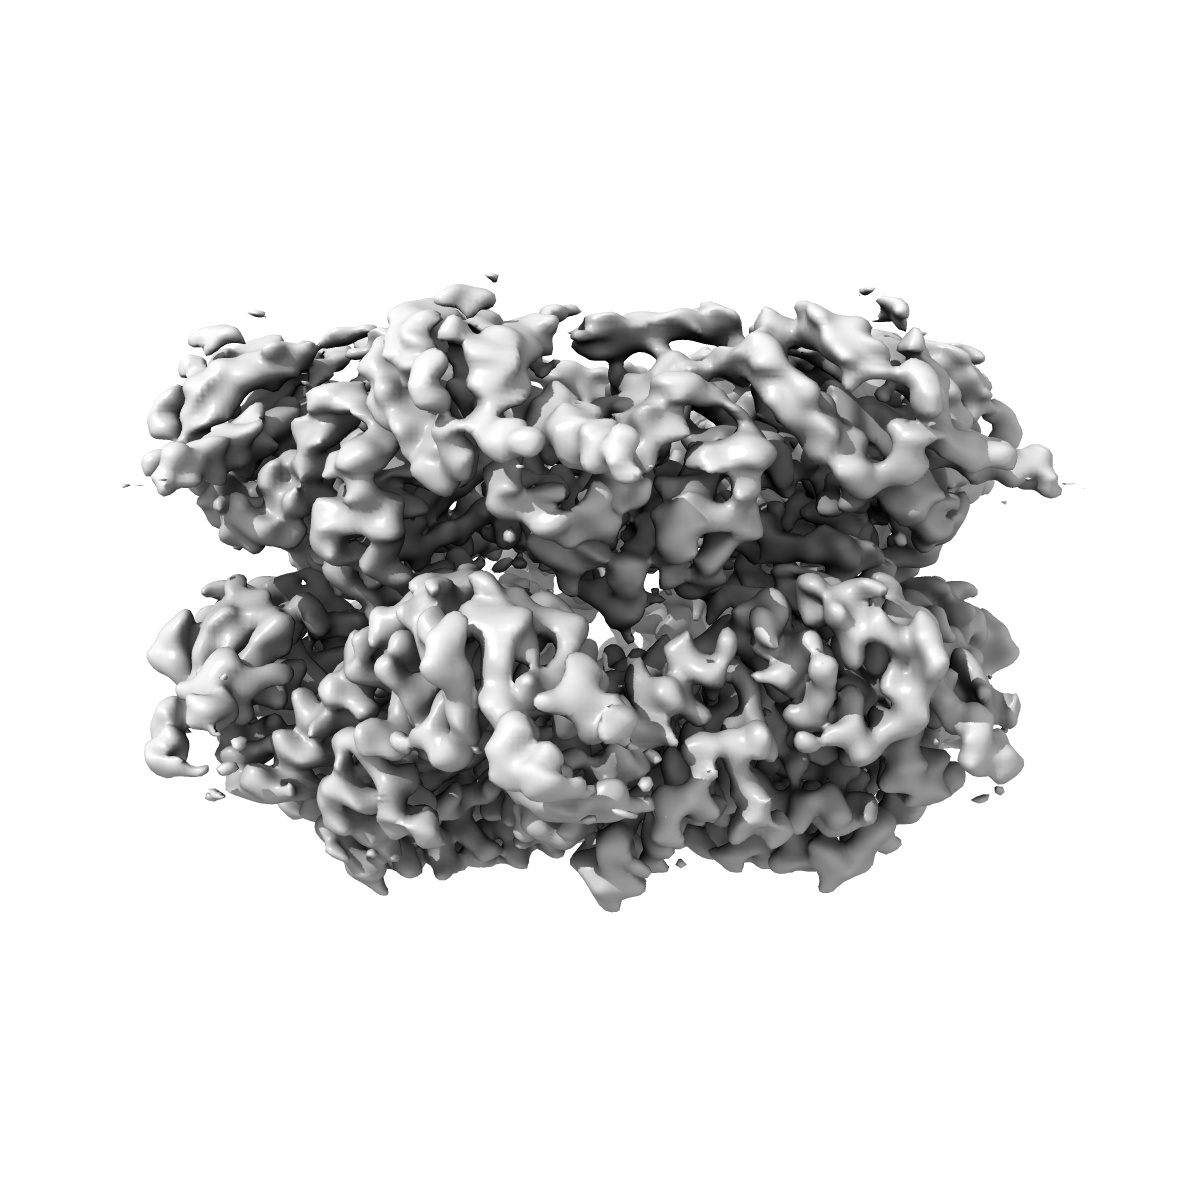

Cryo-EM structure of S. Mansoni p97 bound to compound 739

Single-particle3.06 Å

Sample: Hexamer of p97 conjugated to inhibitor 739

A genome-scale drug discovery pipeline uncovers therapeutic targets and a unique p97 allosteric binding site in Schistosoma mansoni.

(2025) PNAS , 122 , e2505710122 - e2505710122